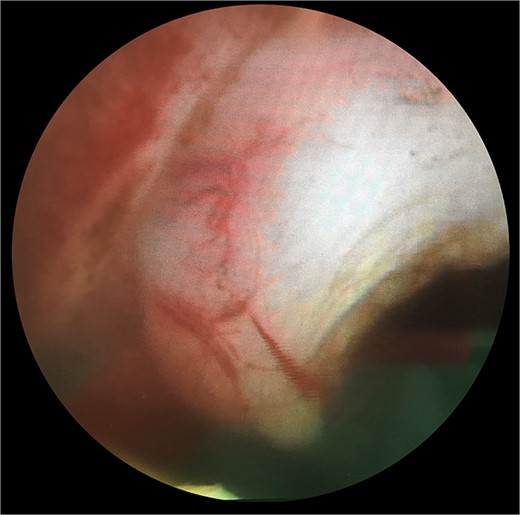

The patient subsequently was booked for diagnostic rigid cystoscopy. On pelvic examination, no palpable mass was felt. Rigid cystoscopy confirmed a cystic structure at the dome that did not look malignant. There was also a mass with normal overlying bladder mucosa on the right side of the bladder neck (Fig. 3), consistent with the soft tissue structure on CT imaging. On resection, the lesion appeared endoscopically as a solid thickened muscular structure, rather than muscle-invasive urothelial cancer.

Endoscopic appearances during transurethral resection of the lesion. Note the presence of normal overlying mucosa and the thickened solid-looking non-papillary appearance.